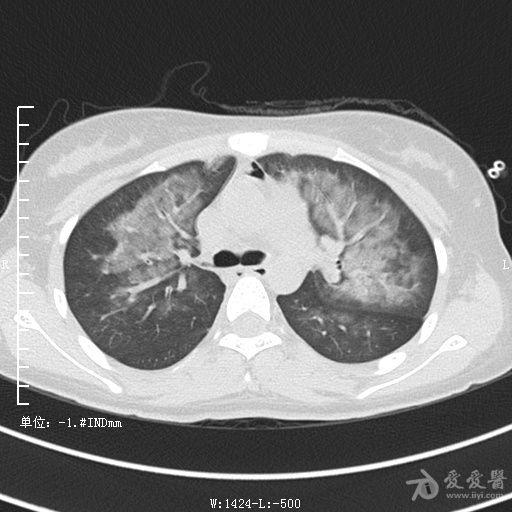

典型支气管扩张及肺水肿CT片

典型支气管扩张肺水肿